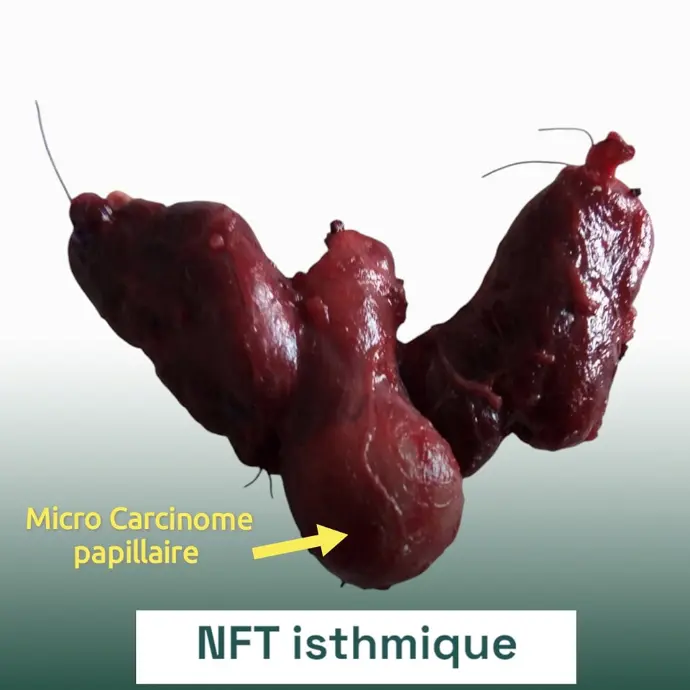

4. العقد الدرقية (Thyroid Nodules):

تكون كتل صغيرة داخل الغدة الدرقية.

غالبًا ما تكون حميدة، لكنها تحتاج إلى الفحص لاستبعاد السرطان.

5. سرطان الغدة الدرقية:

يعتبر نادرًا نسبيًا، ولكنه قابل للعلاج إذا تم اكتشافه مبكرًا.

الأعراض: ظهور كتلة في الرقبة، صعوبة البلع، بحة في الصوت.